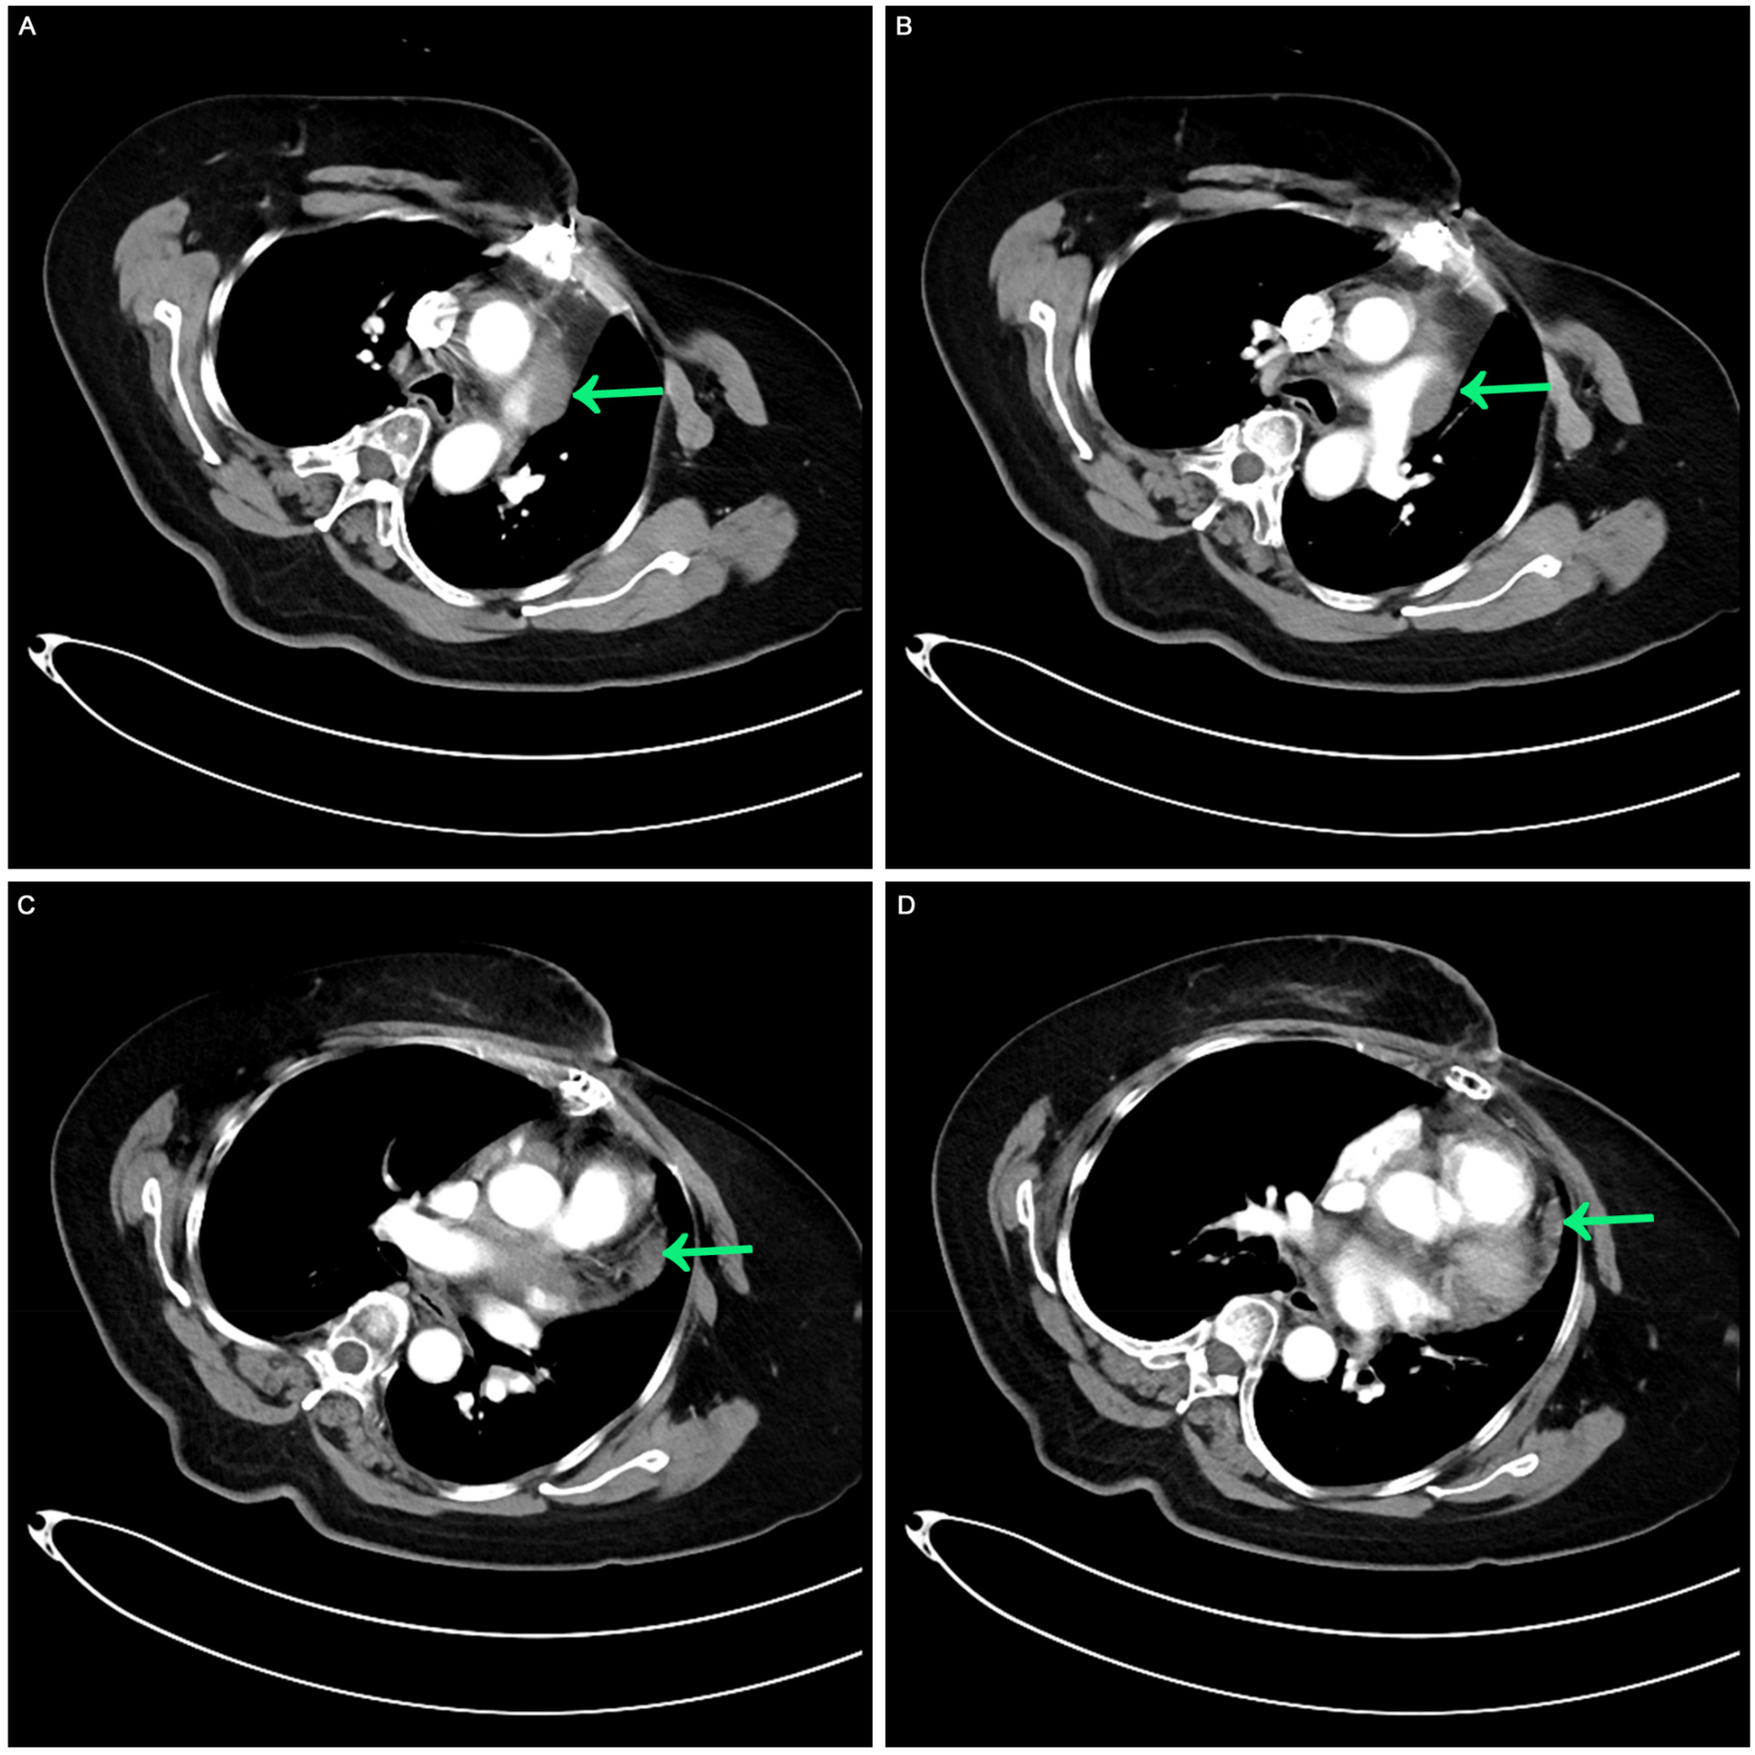

Figure 3

Contrast-enhanced CT after the completion of multimodal treatment. (A,B) The masses around the aorta and pulmonary arteries were retracted. (C,D) A comparable slight thickening of the pericardium was noted, receding from previous observations.

After 3 cycles of chemotherapy, CA125, non-small cell-related antigen, and NSE levels returned to normal. Grade II bone marrow suppression, fatigue, nausea, vomiting, and gastrointestinal reactions occurred during systemic treatment, without other treatment-related side effects. After continuing the follow-up process, the patient had no arrhythmia or dyspnea or pain. CT scan revealed lessened pericardial thickening, normal heart size, no pleural or pericardial effusion except mild elevation of the left diaphragm.